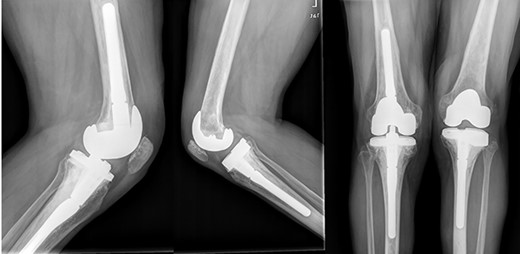

She was referred to our Service to evaluate progressive and disabling pain in both knees. Physical examination revealed bilateral quadriceps atrophy with valgus laxity in the left knee and varus laxity in her right knee. Range of motion (ROM) in both knees was 0°–100°. Standing radiographs showed a pattern of diffuse osteopenia and necrosis (Fig. 1).

Initial both-legs standing radiographs of the knee. It showed a pattern of diffuse osteopenia with areas of sclerosis, lateral extended bone reaction and decreased lateral articular space (Kellgren–Lawrence 3) in the left knee. Bone necrosis with decreased medial articular space (Kellgren–Lawrence 3) were observed in the right knee.